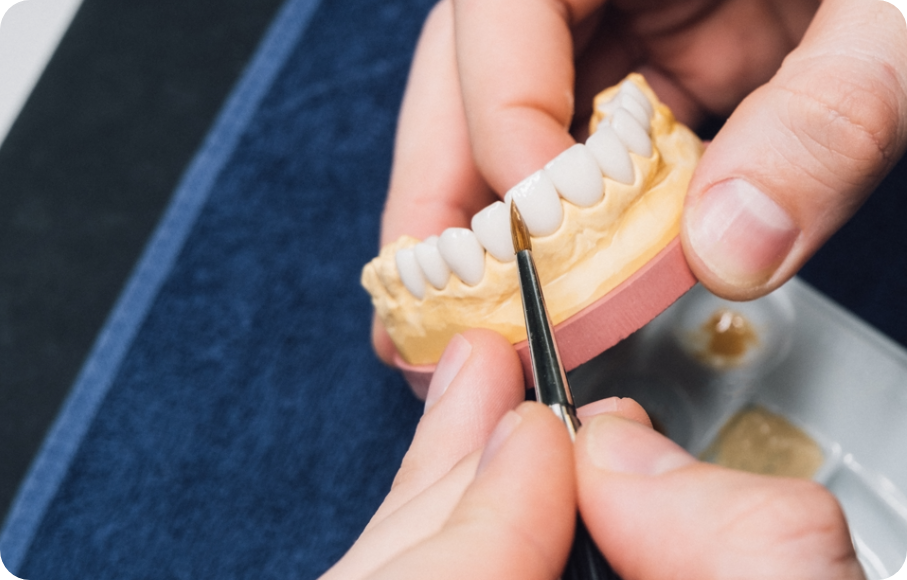

심미보철계의 Ceramist,

국제적인 치과 심미 연구 그룹 오랄디자인 서울 기공소에서 만드는

수제작 라미네이트

얇고 투명한 투과율로 높은 심미성, 높은 강도를 자랑하는 리튬 다이 실리케이트 블럭을

이용하여 적은 치아 삭제로 이상적인 치아를 복원이 가능합니다.

두꺼울수록 치아 삭제량이 많아지는 기존의 방식을 보완한

매우 얇고 치아에 잘 맞는 0.1mm 두께 보철로 자연스러운 라미네이트를 진행합니다.

심미보철 진행 후 가장 걱정되는 부분인 변색 부분에서도,

치료 이후 변색과 착색이 적어 오랫동안 높은 지속성을 경험하실 수 있습니다.